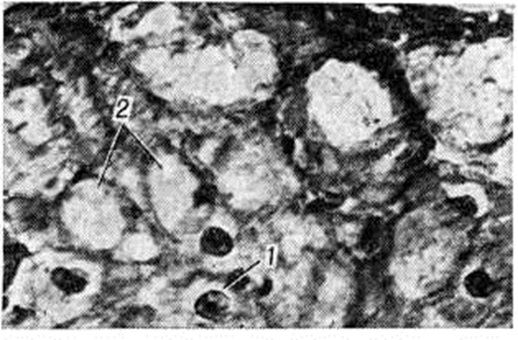

Гистологический исследование выявляет резко гипертрофированные мышечные волокна, короткие и широкие, с уродливыми гиперхромными ядрами. От вторичных функциональный гипертрофий сердечной мышцы (при гипертонической болезни, врождённых и приобретённых пороках) идиопатическая гипертрофия, особенно асимметричная локальная её разновидность, отличается атипизмом общей микроструктуры миокарда вследствие нарушения взаимной ориентации мышечных волокон; они располагаются хаотично, под углом друг к другу, образуют завихрения вокруг соединительнотканных прослоек. Иногда миоциты образуют своеобразные мышечные узлы, включённые в мышечную ткань обычного строения, что даёт основание для представления о них как о пороках развития — гамартомах (рисунок 9). Этот атипизм иногда виден и на поверхности анатомических разрезов участков локальной гипертрофии. Обычна картина дистрофии мышечных клеток с вакуолизацией перинуклеарных зон.